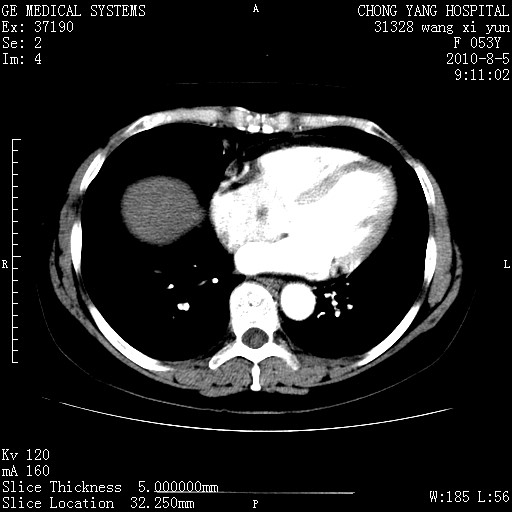

标题: CT28214:F41Y 血尿二十天,建议盆腔平扫加增强。

片子搞错了吧?和上一个是同一张片子。

胆管细胞ca?

1)考虑肝左叶胆管细胞癌。2)脂肪肝。

支持胆管细胞ca。